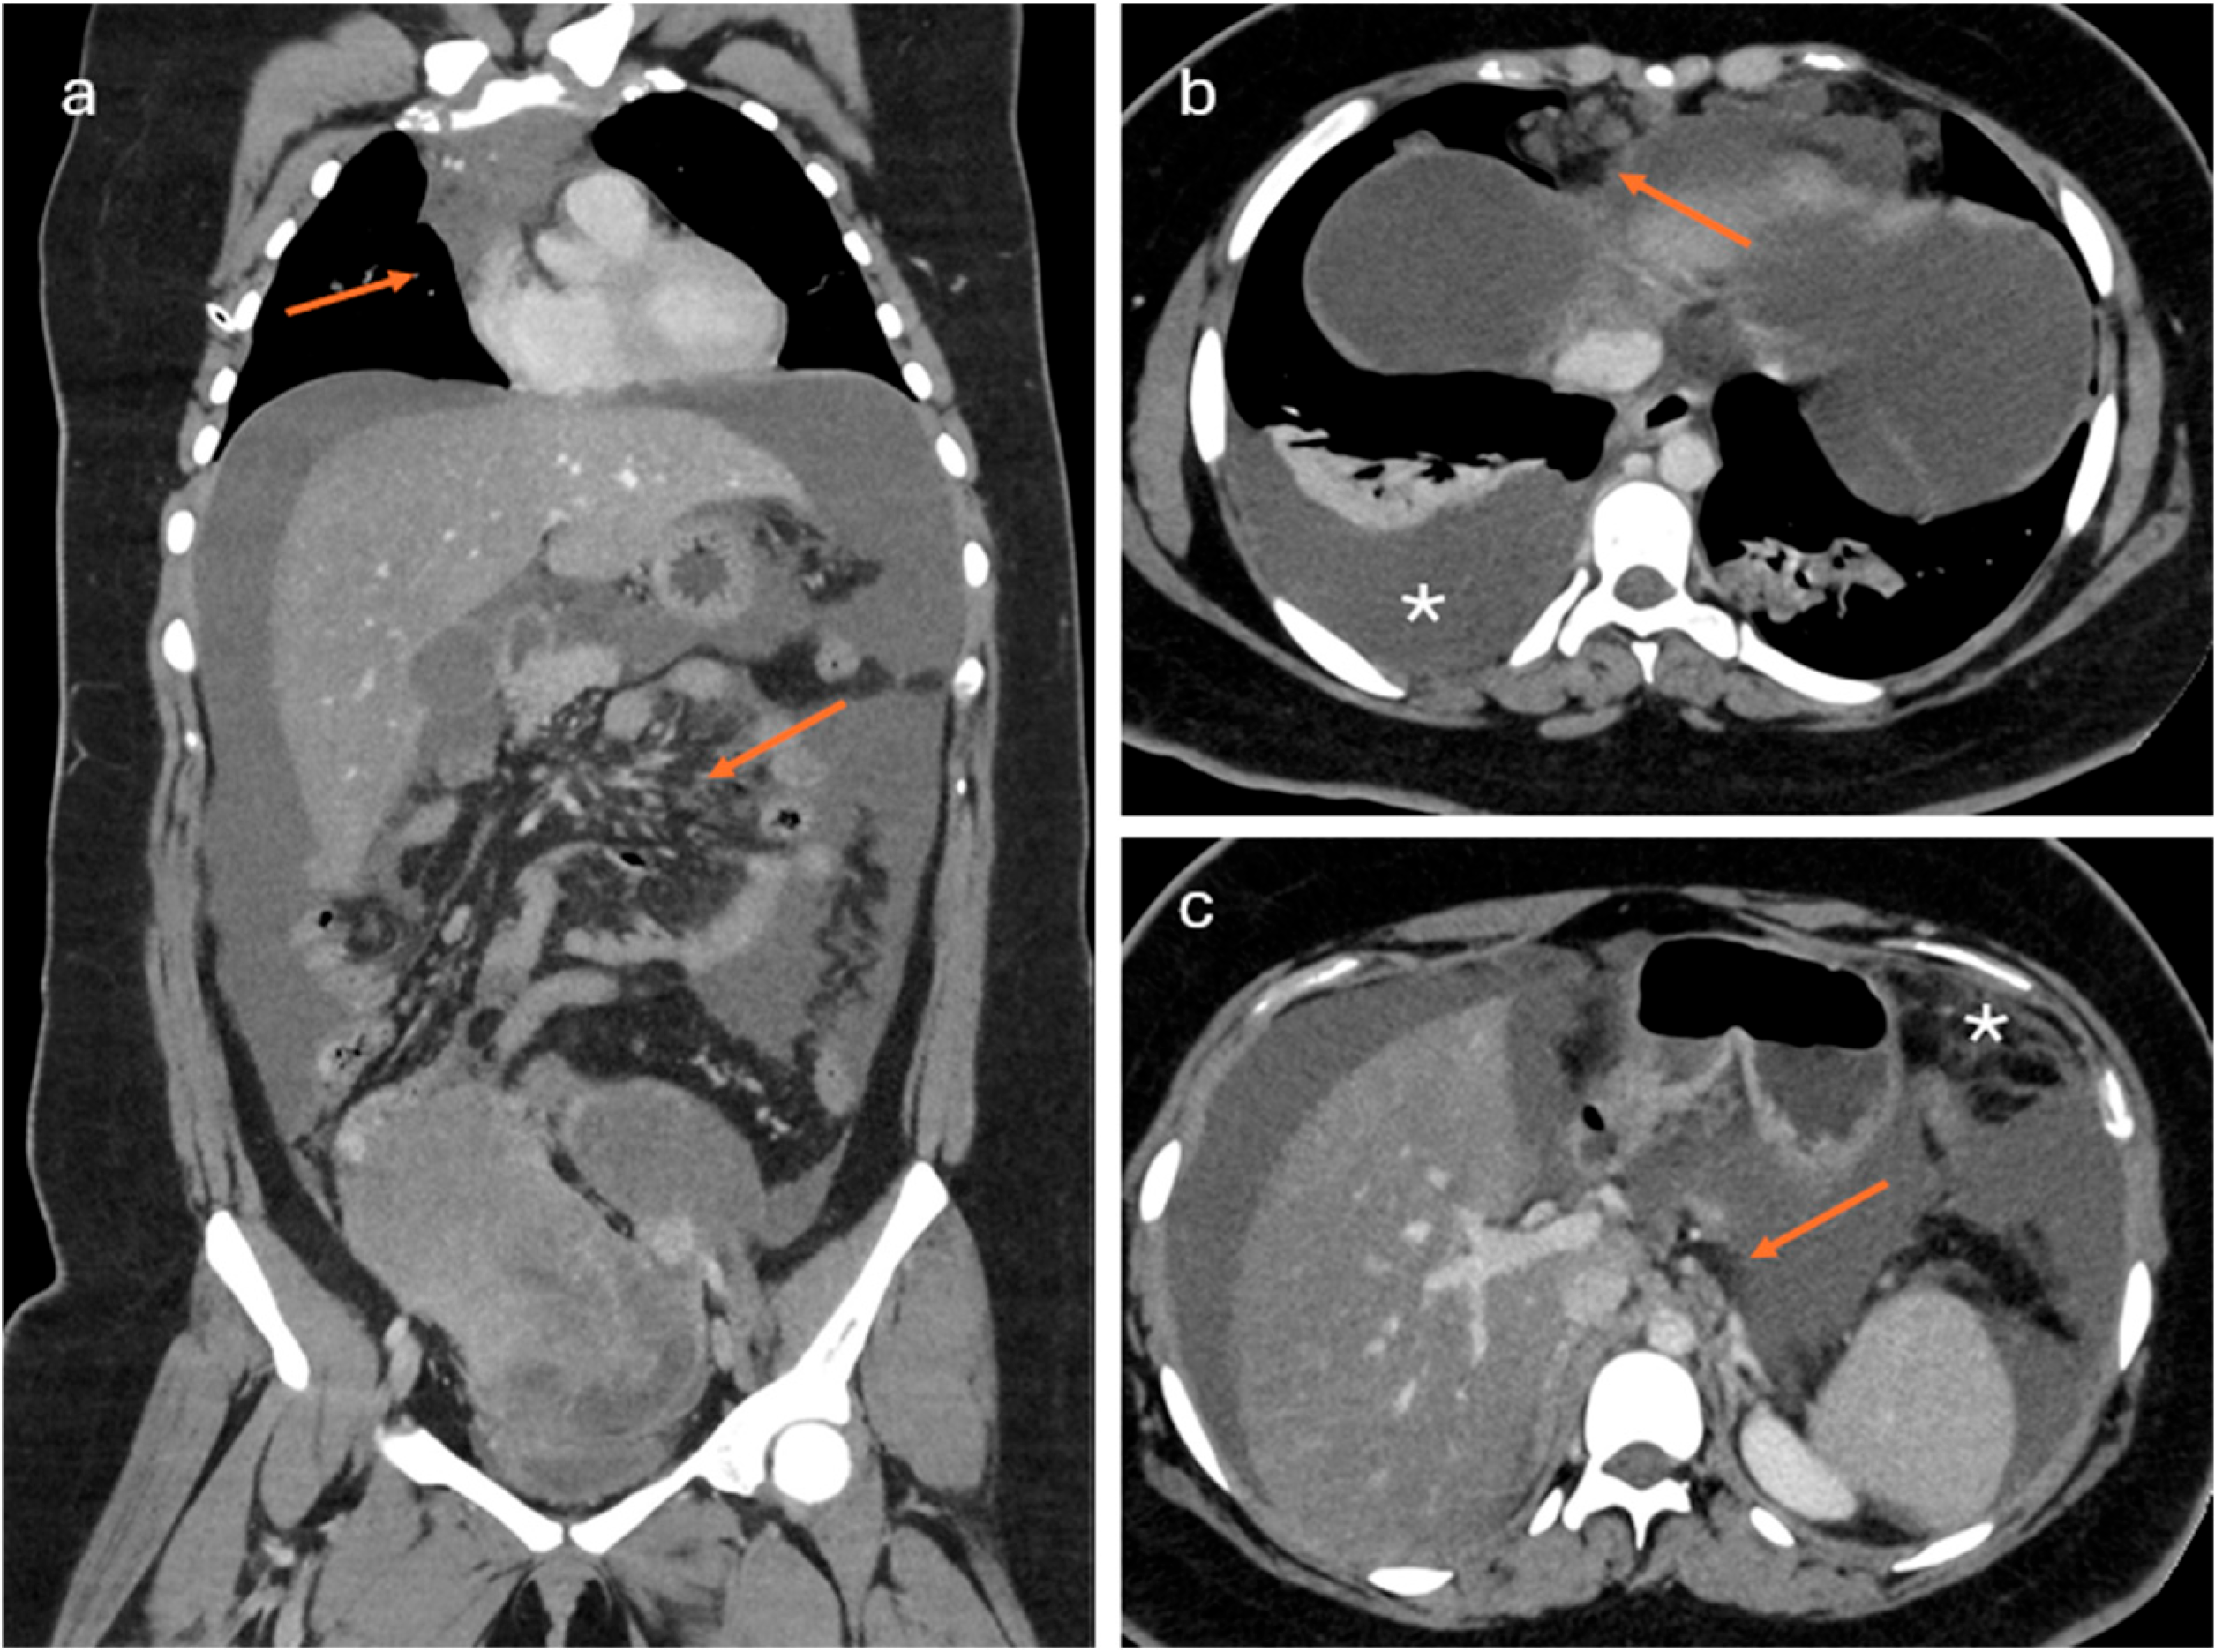

2.2. CT Imaging

- Lesions associated with the presence of peritoneal implants and/or secondary disease localization (Figure 6)

- Prediction of disease spread at diagnosis: AI can automate the process of image segmentation, i.e., the isolation and analysis of suspicious areas in medical images. This segmentation allows radiologists to focus more accurately and quickly on potentially pathological areas. Indeed, although CE-CT is the gold standard for staging ovarian cancer, it has accuracy limitations in identifying small peritoneal implants (<1 cm) and localizations in specific areas such as the small bowel and mesentery. In addition, lesions are often “unmeasurable” according to RECIST 1.1 criteria [68]. Several studies describe how AI can predict the presence of peritoneal carcinosis and lymph node metastasis in HGSOCs on both CT and MR imaging by integrating radiomics with both clinical and laboratory factors such as age and CA-125 blood-levels [69,70,71].